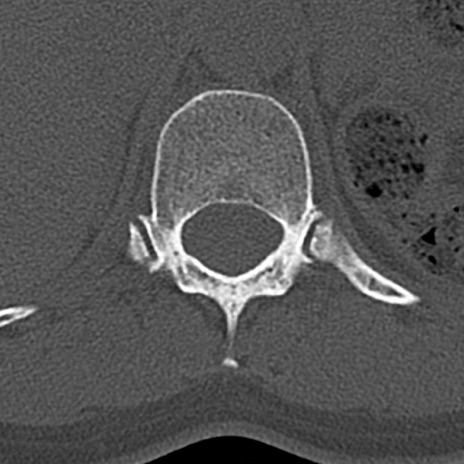

【整形】TIPS症例4 腰椎CT(横断像)

腰椎CT

横断像と矢状断像